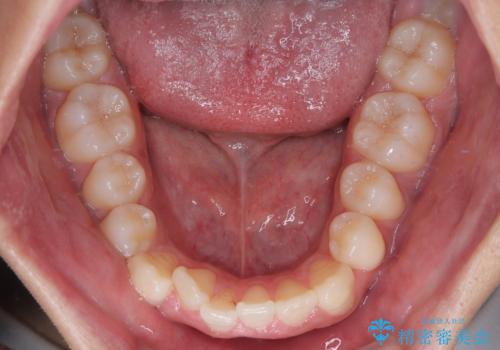

- 「上下の前歯がガタガタしているのが気になる」とのことで来院された患者様です。

上下顎前歯部に叢生(歯の重なり・ガタつき)を認め、見た目だけでなく、歯磨きのしにくさも気にされて来院されました。

- 矯正治療後の保定が不十分だと後戻り(元の位置に戻ろうとする動き)をします